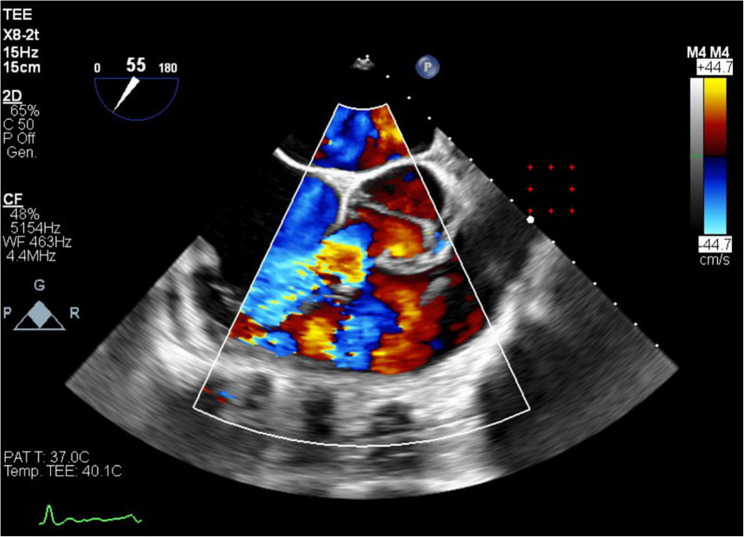

35岁男性,无明显心血管病史,心悸复发。最初的超声心动图评估显示偏心左心室肥厚,轻度收缩功能障碍,怀疑室间隔缺损,二尖瓣主动脉瓣和右心室扩张。经食管超声心动图显示右冠状窦动脉瘤样扩张伴主动脉-心房/心室瘘,经增强计算机断层血管造影进一步证实。冠状动脉造影发现单冠状动脉异常,左冠状动脉占优势,右冠状动脉缺失。手术修复成功关闭瘘,术后主动脉返流轻微。随访一年,心脏尺寸和功能恢复正常,主动脉瓣返流稳定。基因测序未发现可识别的突变。由于与二尖瓣主动脉瓣和冠状动脉异常相关的并发症的潜在风险,建议定期监测。

A 35-year-old male, without significant cardiovascular history, presented with recurrent palpitations. Initial echocardiographic evaluation demonstrated eccentric left ventricular hypertrophy, mild systolic dysfunction, suspicion of a ventricular septal defect, bicuspid aortic valve, and right ventricular dilation. Transesophageal echocardiography revealed an aneurysmal dilation of the right coronary sinus with an aorto-atrial/ventricular fistula, further confirmed by contrast-enhanced computed tomography angiography. Coronary angiography identified a single anomalous coronary artery with left dominance and absence of the right coronary artery. Surgical repair successfully closed the fistula, with mild post-operative aortic regurgitation. Follow-up at one year indicated normalization of cardiac dimensions and function, with stable moderate aortic valve regurgitation. Genetic sequencing found no identifiable mutations. Regular monitoring was recommended due to the potential risk of complications related to the bicuspid aortic valve and coronary anomaly.